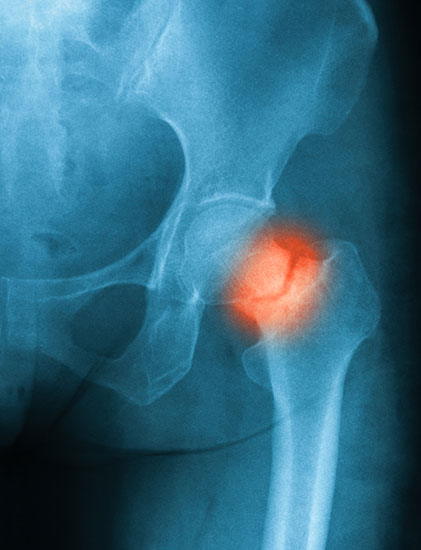

hip fracture x-ray

Hip fractures are very serious injuries. Seek immediate medical attention at your nearest emergency room if you suspect you have a hip fracture. Your doctor will take your medical history and conduct a physical examination, as well as order imaging tests like X-rays to determine if you have a hip fracture.